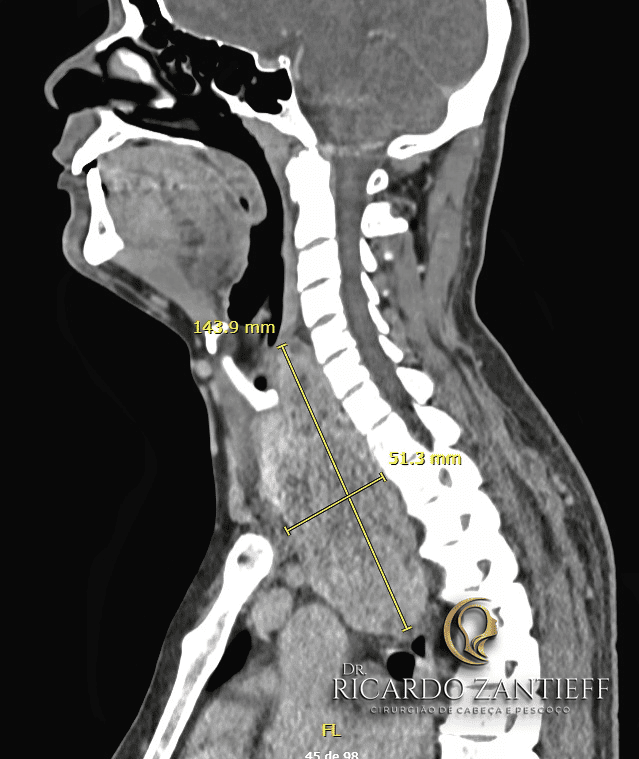

Bócio mergulhante: quando a tireoide cresce para dentro do tórax

Um subtipo importante é o bócio mergulhante, quando a tireoide cresce para dentro do tórax.

Esse tipo de bócio pode ser perigoso, pois comprime estruturas intratorácicas (traqueia, vasos sanguíneos), causando sintomas graves.

O tratamento cirúrgico nesses casos pode ser mais complexo. Em alguns pacientes, o bócio pode ser retirado pelo acesso cervical, mas em situações de crescimento extenso pode ser necessário até abrir o tórax (esternotomia) para remoção completa.